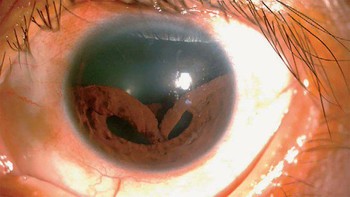

Cedera mata menyebabkan iris rusak. Foto: Twitter/creepy_org